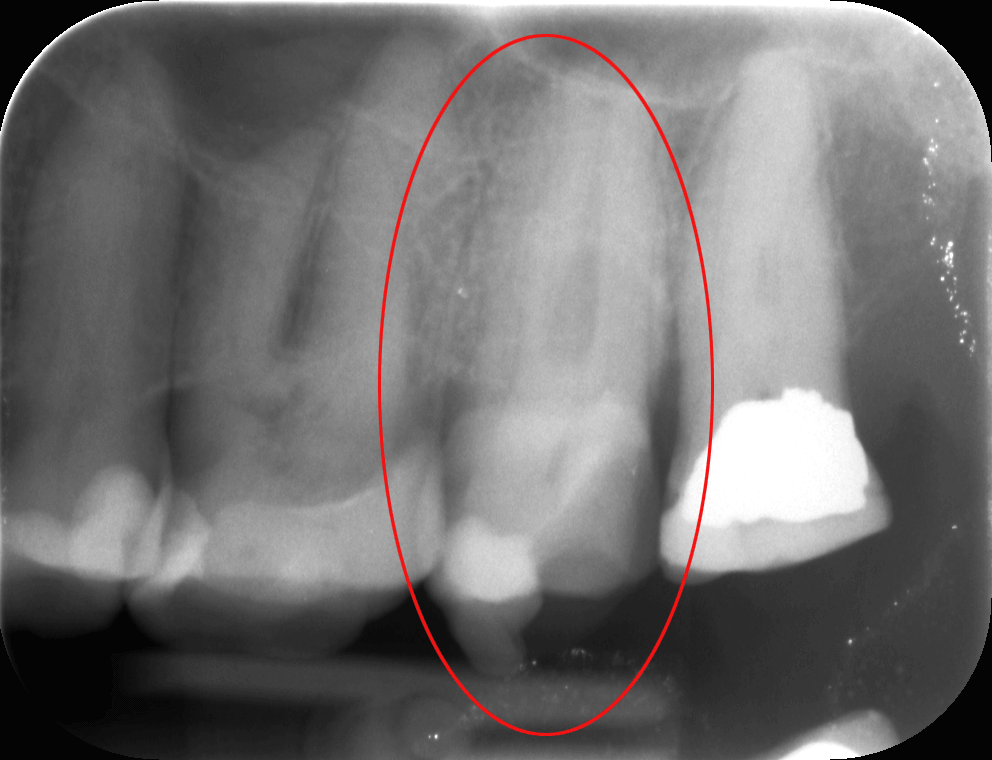

Az 50-es éveit taposó, fiatalos hölgypáciensünk azért kereste fel rendelőnket, mert a bal felső 7-es foga (az első képen pirossal bekarikázva) állandó sajgását, érzékenységét már tűrhetetlennek érezte.

Dr. Molnár Katalin, a mikroszkópos gyökérkezelések specialistája megvizsgálta a röntgenfelvételt, amelyen az érintett fognál 3 foggyökeret lehetett kivenni. Ám fennállt a gyanú, hogy a panaszok okát egy negyedik, „láthatatlan” foggyökérben kell keresni. Az őrlőfogaknál egyáltalán nem számítanak ritkaságnak a rendkívül vékony, szabad szemmel nem vagy alig látható, tekervényes foggyökércsatornák. A kezelőorvos a mikroszkópos kezelés mellett döntött, hogy utánajárjon, van-e „láthatatlan” foggyökércsatornája a panaszos fognak.